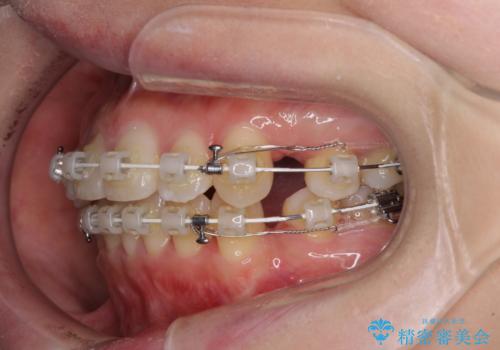

- 矯正装置

- 審美装置

- 口元の突出感と口の閉じにくさを気にして来院された患者様です。

上下左右第一小臼歯4本を抜歯し、ワイヤー装置にて口元を引っ込めるよう矯正治療を行うこととしました。

2年~2年半が治療期間の目安でしたが、順調に治療が進み、1年9か月で満足のいく歯列となりました。